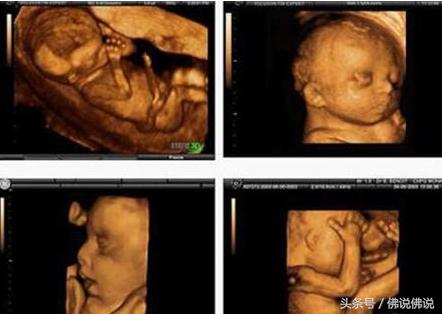

四维彩超供给了包含腹部、血管、小器官、产科、妇科、胎儿彩超图泌尿科、新生儿和儿科等多范畴的多方面的使用。其结果是:能够显现您未出世的宝宝的实时动态活动图画,或许其它人体内脏器官的实时活动图画。